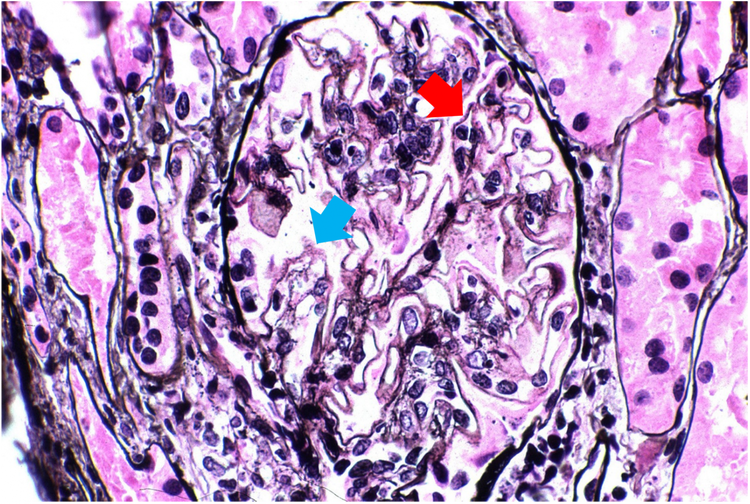

Whereas in Figure 2, samples from LN class 5 advanced-stage patients show diffuse holes (blue arrow) and small spikes (red arrow) along glomerular basement membranes.3

Figure 1. LN class 1 kidney sample biopsy sample, stained with Jonas silver stain.